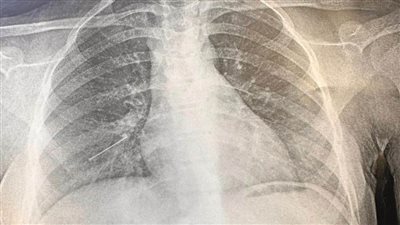

إنقاذ حياة فتاة ابتلعت "دبوس طرحة" بمستشفى بنها الجامعي

الثلاثاء 28/مارس/2023 - 03:50 م